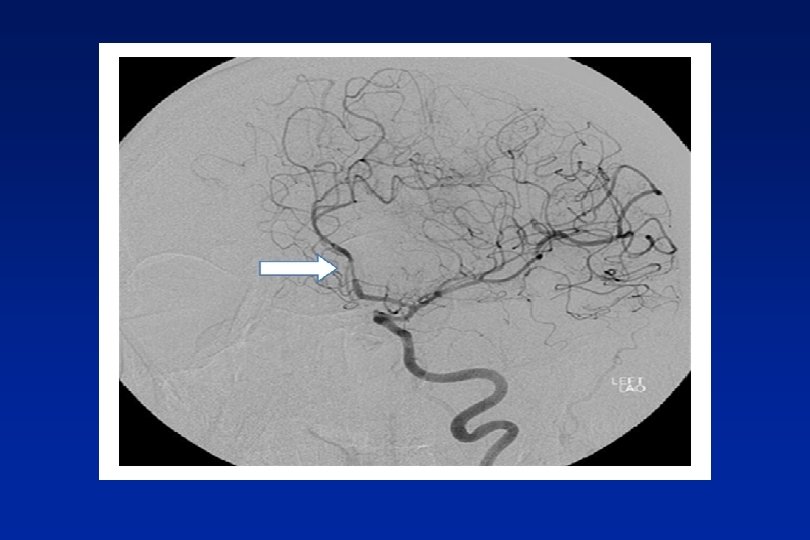

Sub Arachnoid - thunderclap headache

Thunderclap headache - RVS n lasts 1 -3 mths. n Primary or secondary n Normal CT, LP. Needs CT angio. n Can get complications